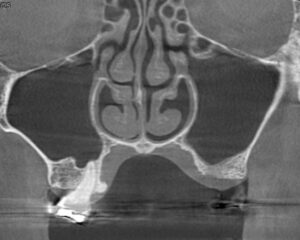

今回、左上の奥歯の違和感と鼻閉感(鼻声)を訴えられた患者様に対してCT撮影を行いました。

重度の歯周病になった左上奥歯の周囲の骨は大きく吸収し、左側の上顎洞には膿が溜まった状態でした。

右側の上顎洞の状態(正常な場合は空洞内全体が黒く写る)に比べて左側は白く濁っていましたが、左側の上顎洞の空気の通り道は細いながらも通じており、鼻が原因ではなく歯が原因の上顎洞炎であると診断しました。

原因の歯は残念ながら抜歯となりましたが、原因の歯を抜歯したことで上顎洞炎の症状は完全に消失し、抜歯した部位の骨も部分的に回復しました。